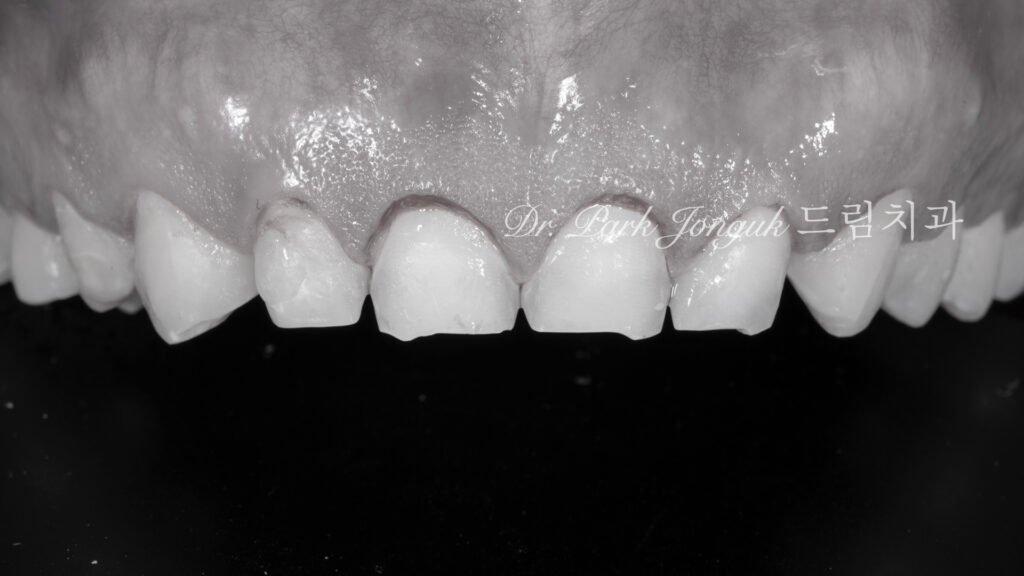

3. 정밀 진단 단계: Prescription & Inspection (사진 2, 3)

3.1 왁스업(Wax-up)을 통한 볼륨 재설계

[사진 2, 3 참조] 무삭제 방식은 삭제를 하지 않는 대신, 보철물이 얹어졌을 때의 부피감을 완벽하게 제어해야 합니다.

- 디지털 분석: 환자의 안면 구조와 스캔 데이터를 결합하여 삭제 없이도 입술 돌출감이 없는 최적의 두께를 산출합니다.

- 왁스업 결과물: 이를 실물 모형화하여 저작 시 간섭 여부와 심미적 만족도를 사전에 철저히 검증합니다.